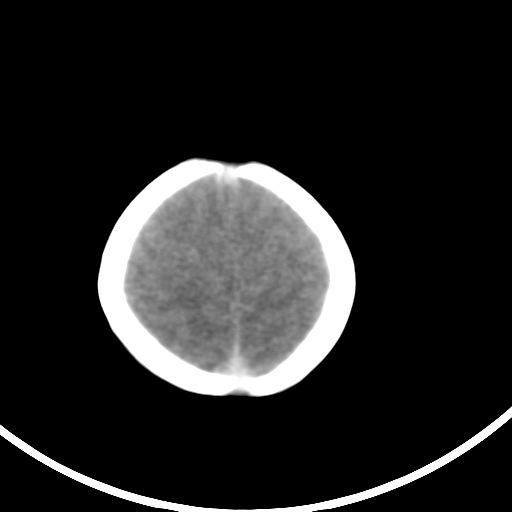

新生儿3天,超过预产期5天剖宫产,有缺氧病史,具体评分不详,现反应差,肌张力低,前囟平,原始反射存在,无苦闹等。

正常

颅底骨质影,正常颅脑表现。

颅底骨质影,正常颅脑表现.

正常颅脑表现。

kaolv小脑幕,后纵裂区蛛网膜下腔出血;轻度脑肿胀

未见明显异常

颅脑ct平扫未见异常。

新生儿正常颅内表现